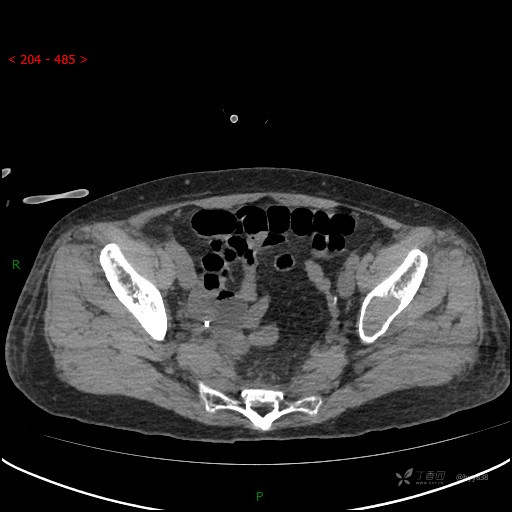

CT平扫